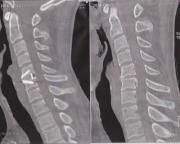

今回、10代の時の怪我が原因で押しつぶされて飛び出した椎間板ヘルニア完全におさらばできました!

2,3年前に一度、右腕の力が入らなくなってしまい頸椎症性神経根症と診断され後方からの除圧術を受けました。

その病院に行くと頸椎症性脊髄症と診断されこのまま放っておくと歩けなく可能性もあると伝えられたのでオペを決心しました。